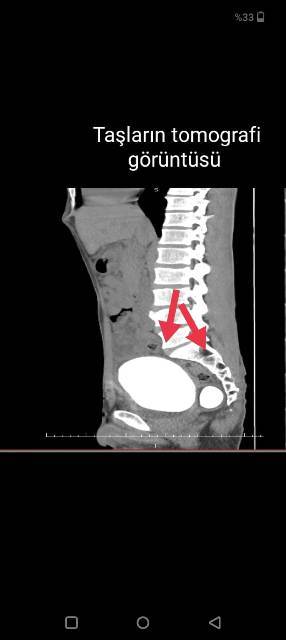

Karaman'da "idrar yaparken yanma" şikayeti ile hastaneye başvuran bir hastanın mesanesinden, bir kilo 50 gram taş çıkartıldı. Karaman'da ikamet eden 27 yaşındaki Barış Yıldız, "idrar yaparken yanma" şikayeti ile Karamanoğlu Mehmetbey Üniversitesi Tıp Fakültesi Karaman Eğitim ve Araştırma Hastanesine başvurdu. Çekilen röntgende hastanın mesanesinde 2 adet büyük çapta taş tespit edildi.Doç. Dr. Güven Erbay ve Dr. Öğretim Üyesi Ahmet Şanlı tarafından yapılan operasyon ile 2 taş alındı.Erbay, yaptığı açıklamada, yapılan tetkiklerle mesanede iki adet taş tespit edilmesi üzerine hastaya acil müdahale ettiklerini belirterek, şöyle konuştu:"Literatürde, tüm dünya genelinde kayıtlara geçen en büyük mesane taşının ağırlığının bin 900 gram olduğu bilinmektedir. Çıkarılan taşların toplam ağırlığı bir kilo 50 gram olarak tespit edildi. Bu büyüklükteki ve ağırlıktaki dev mesane taşının Türkiye sınırları içerisinde çıkarılan en büyük mesane taşı olduğunu düşünmekteyiz."Hastanenin Başhekimi Dr. öğretim üyesi Ahmet Yılmaz ise hastanenin bu tür ameliyatları yapma imkanına ve teknik donanıma sahip olduğunu ifade ederek, "Bundan sonra da bu tür ameliyatları gerçekleştirmeye devam edeceğiz. Bu ameliyatı gerçekleştiren hocalarımıza, emeği geçen herkese teşekkür ediyorum ve tüm hastalarımıza acil şifalar diliyorum." diye konuştu.